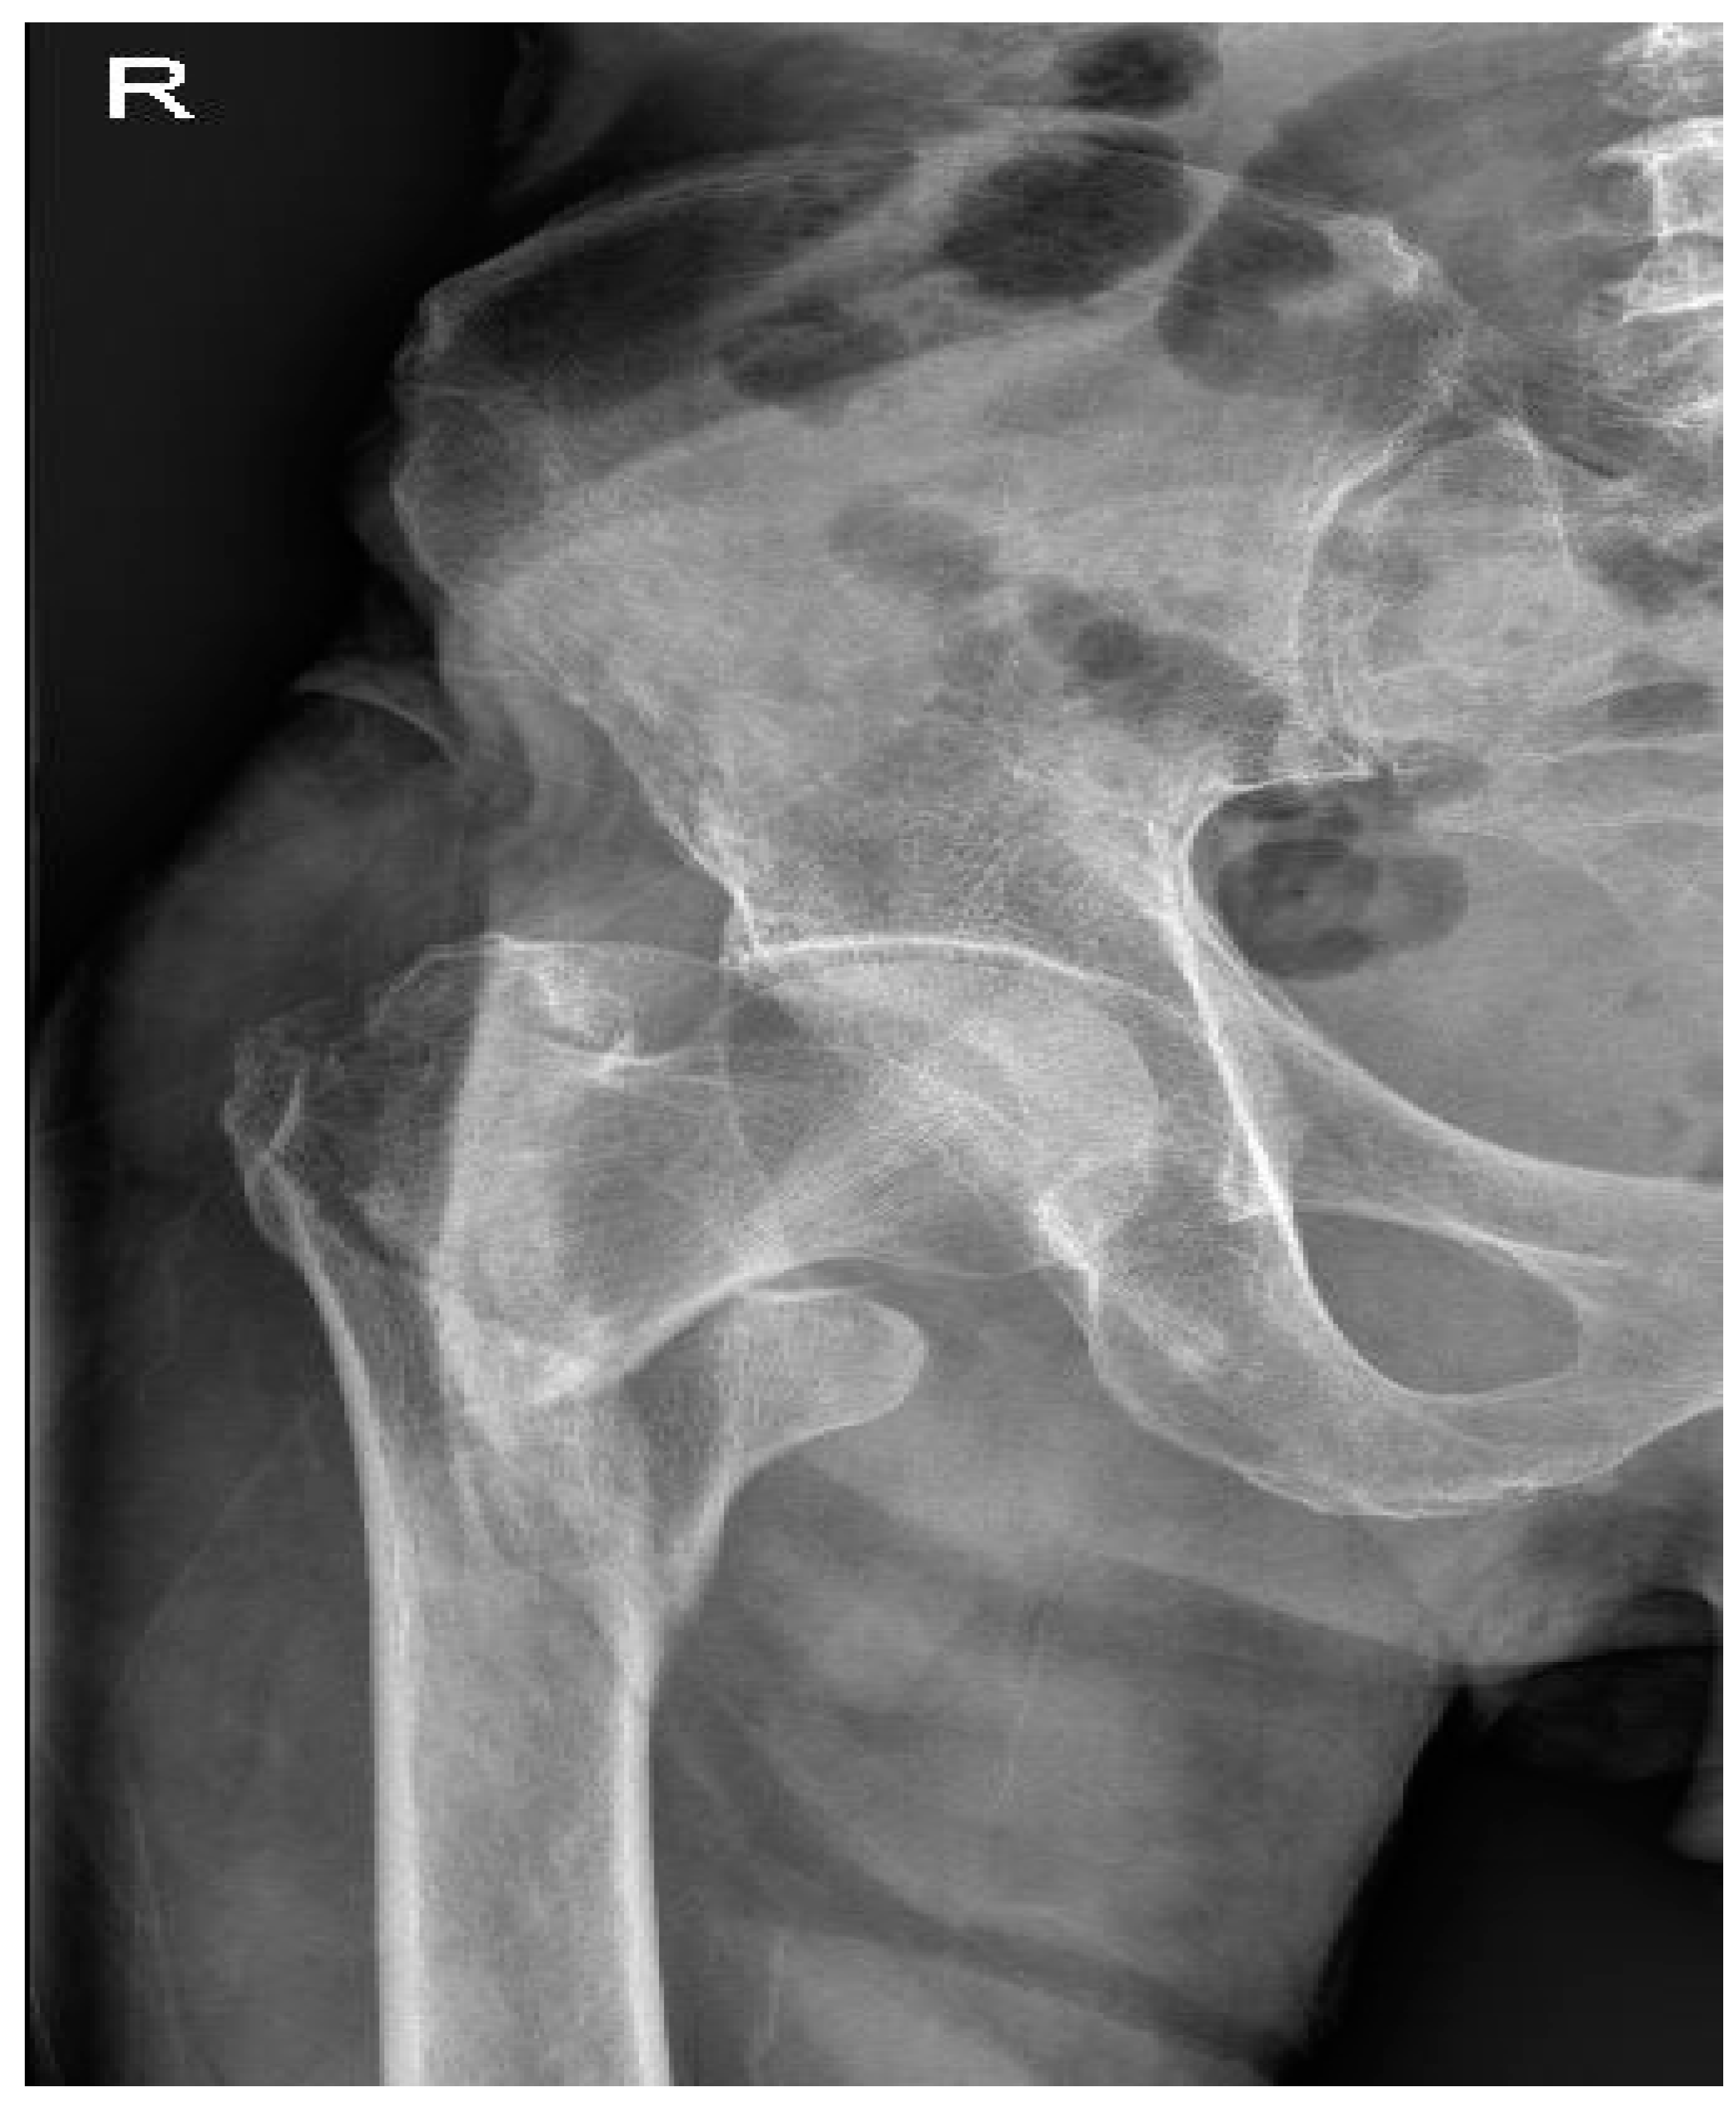

2. Case Presentation